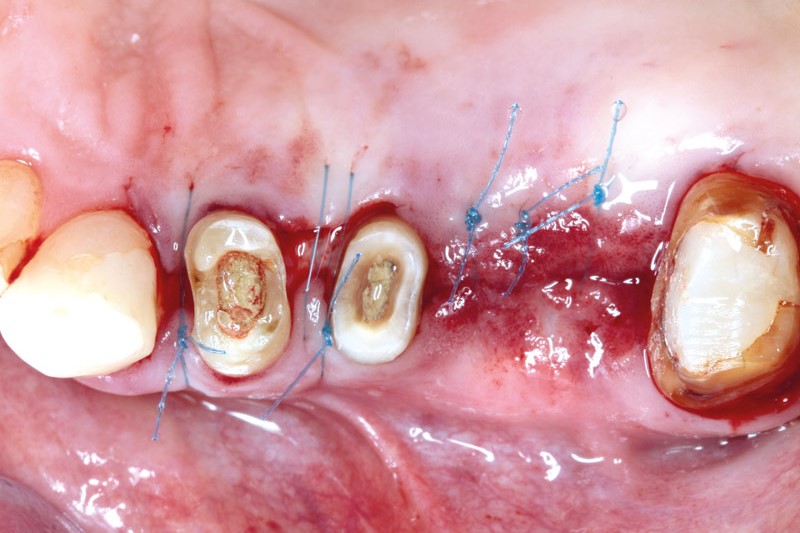

Intrabony defect treated using collprotect® membrane & cerabone® (1) - Cosgarea & Sculean

Pre-surgical probing reveals a deep intrabony defect on the distal aspect of the upper canine.